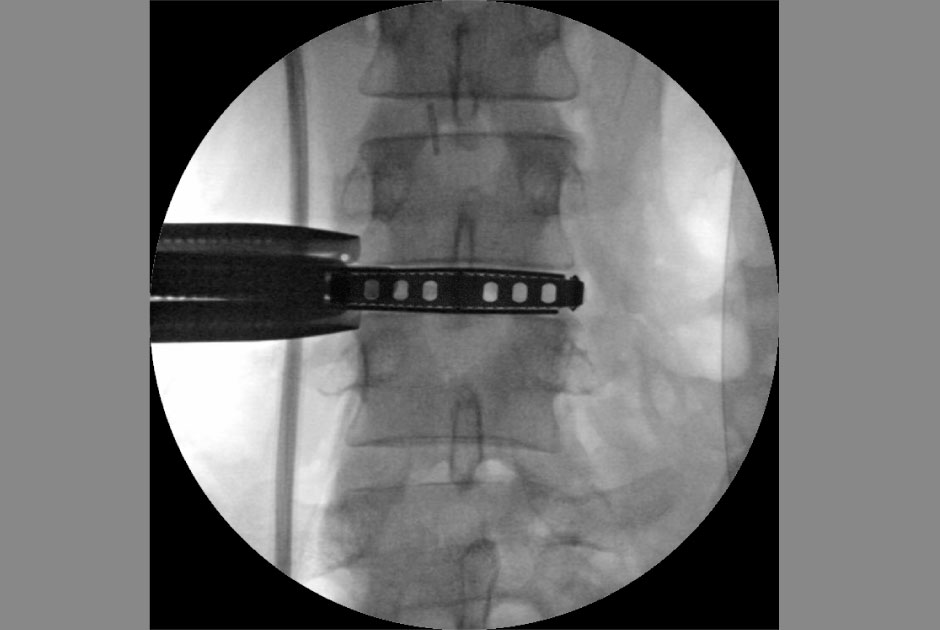

内視鏡下椎間板摘出術

PED / 内視鏡下椎間板ヘルニア摘出術

体への負担が少ない内視鏡下椎間板ヘルニア摘出術

(PED:Percutaneous Endoscopic Discectomy)

当院は、中度~重度の椎間板ヘルニアの治療方法として、体への負担が少ない内視鏡下椎間板ヘルニア摘出術(PED:Percutaneous Endoscopic Discectomy)を取り入れています。

PEDでは、直径6~7mmの鉗子をヘルニアの部位に挿入し、内視鏡画像をモニターに拡大表示しながら行います。

PEDの場合、局部麻酔による手術となり、短時間(1~2時間ほど)で終わります。また、傷口は6~7mm程度で、抜糸も必要ありません。早くて手術翌日には退院できるため、体に優しい手術と言えるでしょう。